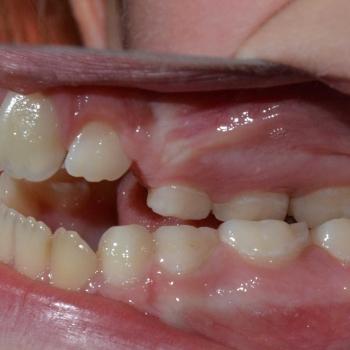

Csenge és édesanyja még vegyesfogazati időszakban, az egyetemen kerestek fel többszörös funkciós és esztétikai problémák miatt. Az első vizsgálat alkalmával súlyos nyitottharapást, keresztharapást, középvonal eltolódást, Angle II. osztályú eltérést, nyelvlökéses nyelést, helyhiányt diagnosztizáltunk, illetve elképesztő ritkaságként felcserélődött szemfog-kisőrlő csírákat találtunk a jobb oldalon.